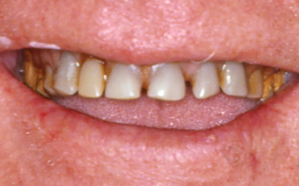

גלריית הצגת מקרים לפני ואחרי